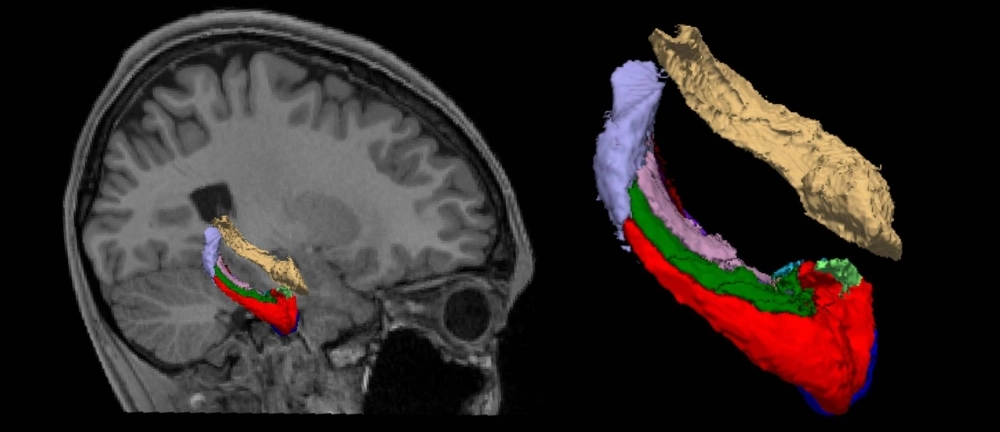

Researchers led by Shinsuke Koike and Lin Cai used analyzed data of about 450 teenagers between 15 and 17 in three municipalities in Tokyo who had undergone MRI scans before and after the state of emergency.